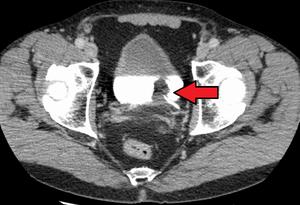

- CT Urography – will detect the presence, depth and type of bladder cancer with functioning of urinary system.

If Transitional Cell Carcinoma – of the Bladder is detected on Biopsy, subsequent evaluation will be done for staging, grading and distant spread of bladder cancer